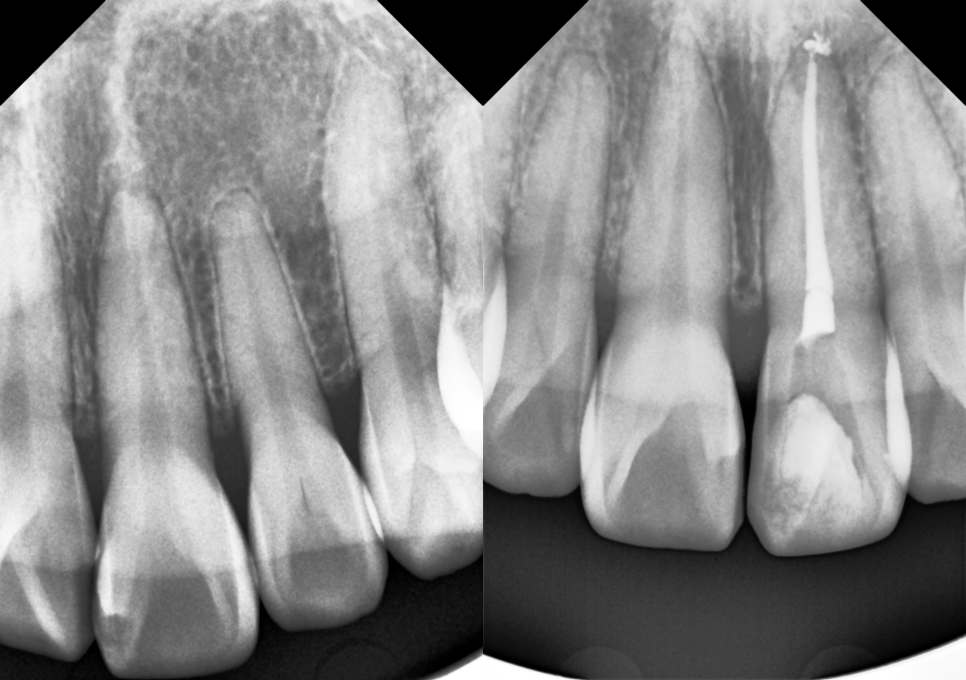

해외에서 넘어지셔서 다치셨는데

귀국 후 바로 저희 치과를 찾아주셨습니다.

아무래도 레진으로 치료해 주는 곳이

많지는 않죠.

이전에 치료를 받은 적이 없는 생니이기 때문에

일단 신경치료를 진행해야 합니다.

2024.10.12.

염증이 없는 경우 신경치료는 당일 마무리 합니다.

바로 미백제를 넣기 위해서.

신경치료는 보통 여러번 오는 게 정석이지만,

그건 충치나 크랙으로 신경관이 오염된 경우고요

감염의 징후가 없는 경우

굳이 여러번 치과에 방문할 필요가 없다고 생각합니다.

single-visit RCT(root canal treatment)라고

부르는 '당일 신경치료 완료' 방법은

실활치 미백에서 굉장히 도움이 됩니다.